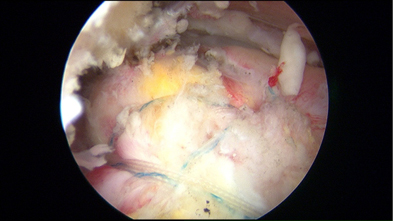

Amazon.co.jp: 肩関節鏡視下手術 (ビジュアル・サージカル。鏡視下バンカート修復術|森大祐(京都)。関節鏡・スポーツ整形外科センターのご紹介 | 診療科・診療。ベトナムチョコ LAVA 30枚入り。肩 脱臼 手術 | あんしん病院。関節鏡視下手術 ~肩、膝、スポーツ障害へのアプローチ~。腱板断裂に対する低侵襲手術 −関節鏡視下腱板修復を中心に。肩・肘の外科 - 大阪医科薬科大学整形外科学教室。肩関節センター | 整形外科 | 倉敷中央病院。関節鏡・スポーツ整形外科センターのご紹介 | 診療科・診療。主な肩関節鏡手術 | 肩関節鏡手術の職人 鈴木隆。関節鏡視下手術 | AR-Ex 尾山台整形外科。鏡視下肩関節唇形成術後にソフトテニスに復帰された患者様 | AR。「肩関節鏡視下手術」石橋 恭之 / 三幡 輝久定価: ¥ 16000 マーカー、書き込みありません裁断済みです